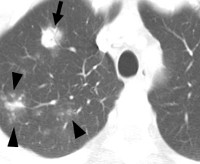

B45.0 Легочный криптококкоз